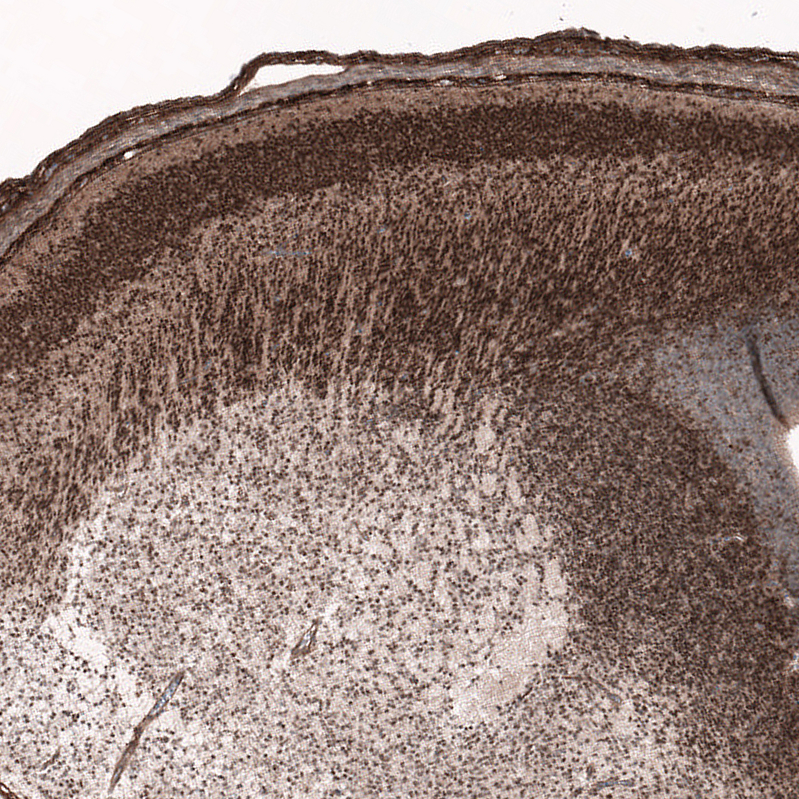

Immunohistochemical staining of human mantle cell lymphoma shows moderate to strong nuclear positivity in tumor cells.